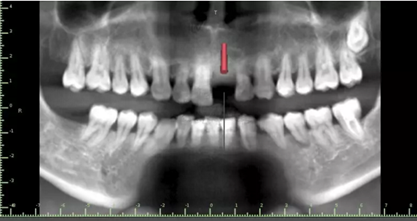

1.術(shù)前CT

術(shù)后CT